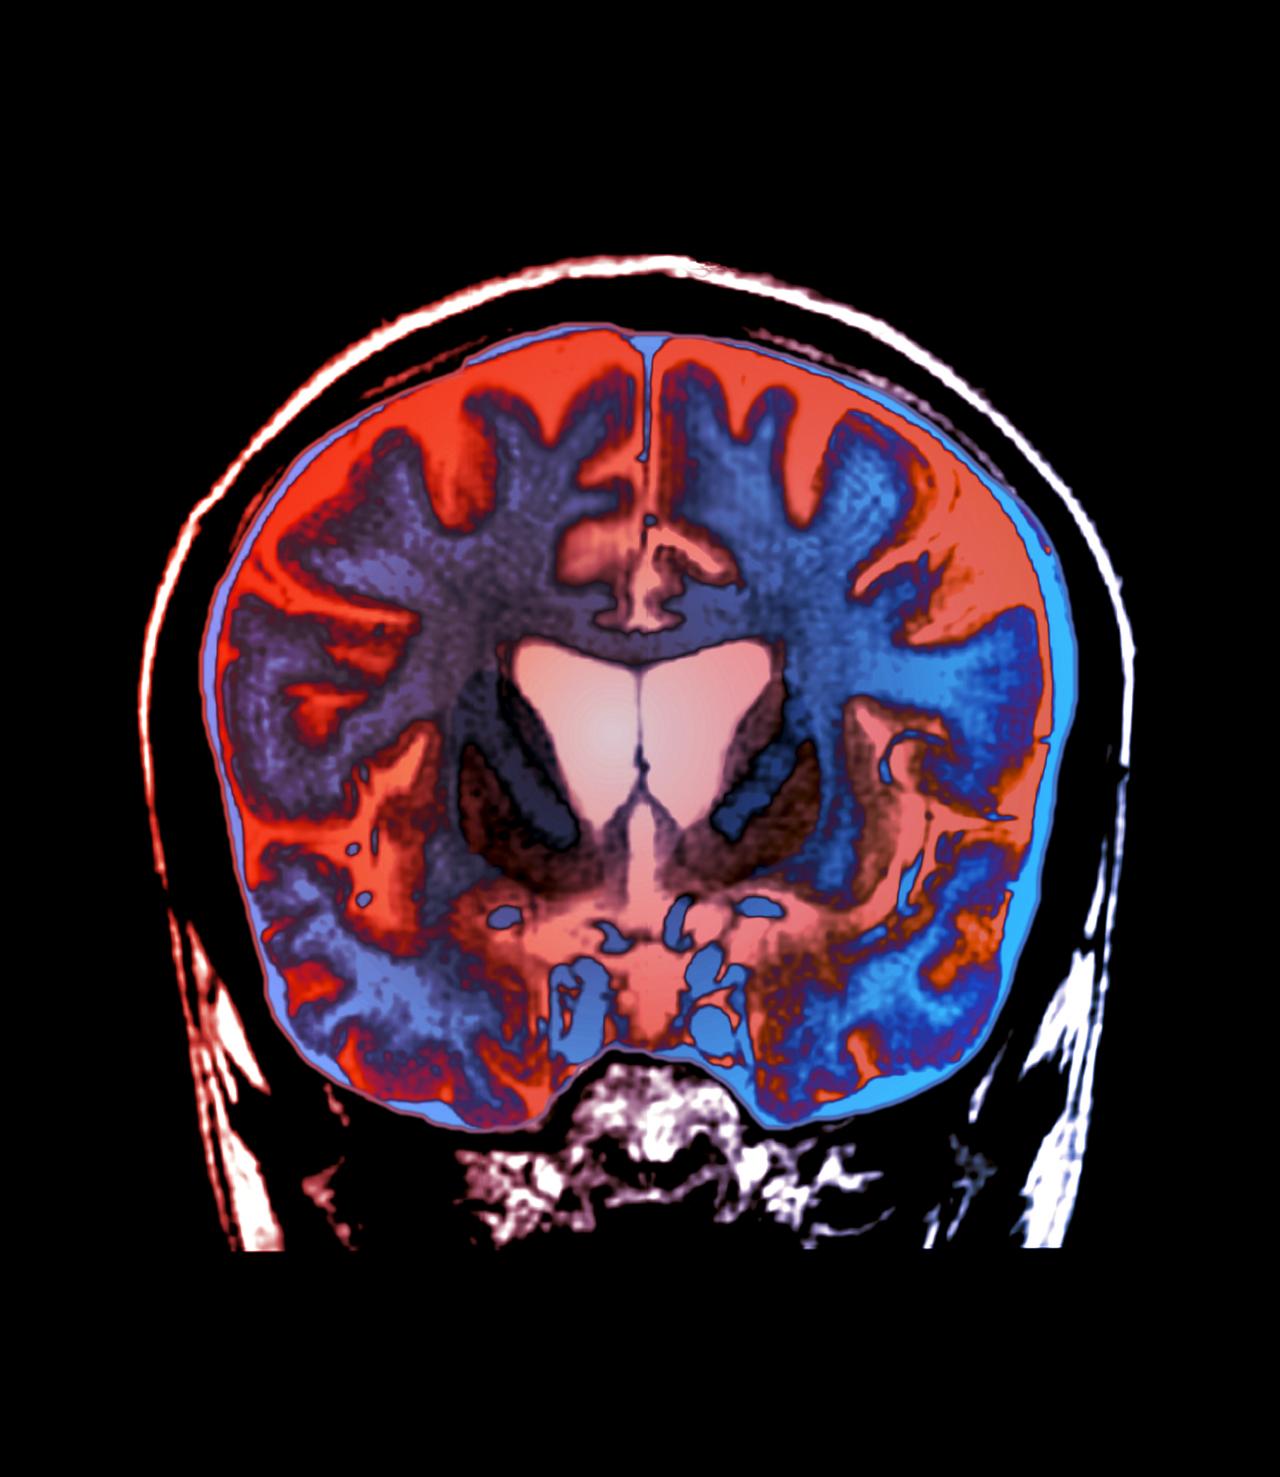

A betegség pontos oka ismert: az úgynevezett HTT gén mutációja miatt hibás fehérje képződik, amely az agy striatum nevű részében rakódik le, és sejtpusztulást okoz. Ez elméletben egyszerű célponttá teszi a Huntington-kórt a gyógyszerfejlesztők számára, ám a gyakorlatban meglepően nehéz volt hatásos kezelést találni.

Az AMT-130 génterápiát egyetlen – bár invazív – beavatkozással juttatják az agyba: katéterek segítségével a striatumba fecskendeznek be a szervezet számára önmagában ártalmatlanított vírusokat, amelyek genetikai “csomagot” szállítanak a célsejtekbe. Ezek a neuronok ezután folyamatosan mikrosRNS-t termelnek, amely célzottan lebontja a hibás fehérje előállításának genetikai üzenetét, vagyis tartósan csökkenti a kóros huntingtin fehérje mennyiségét.